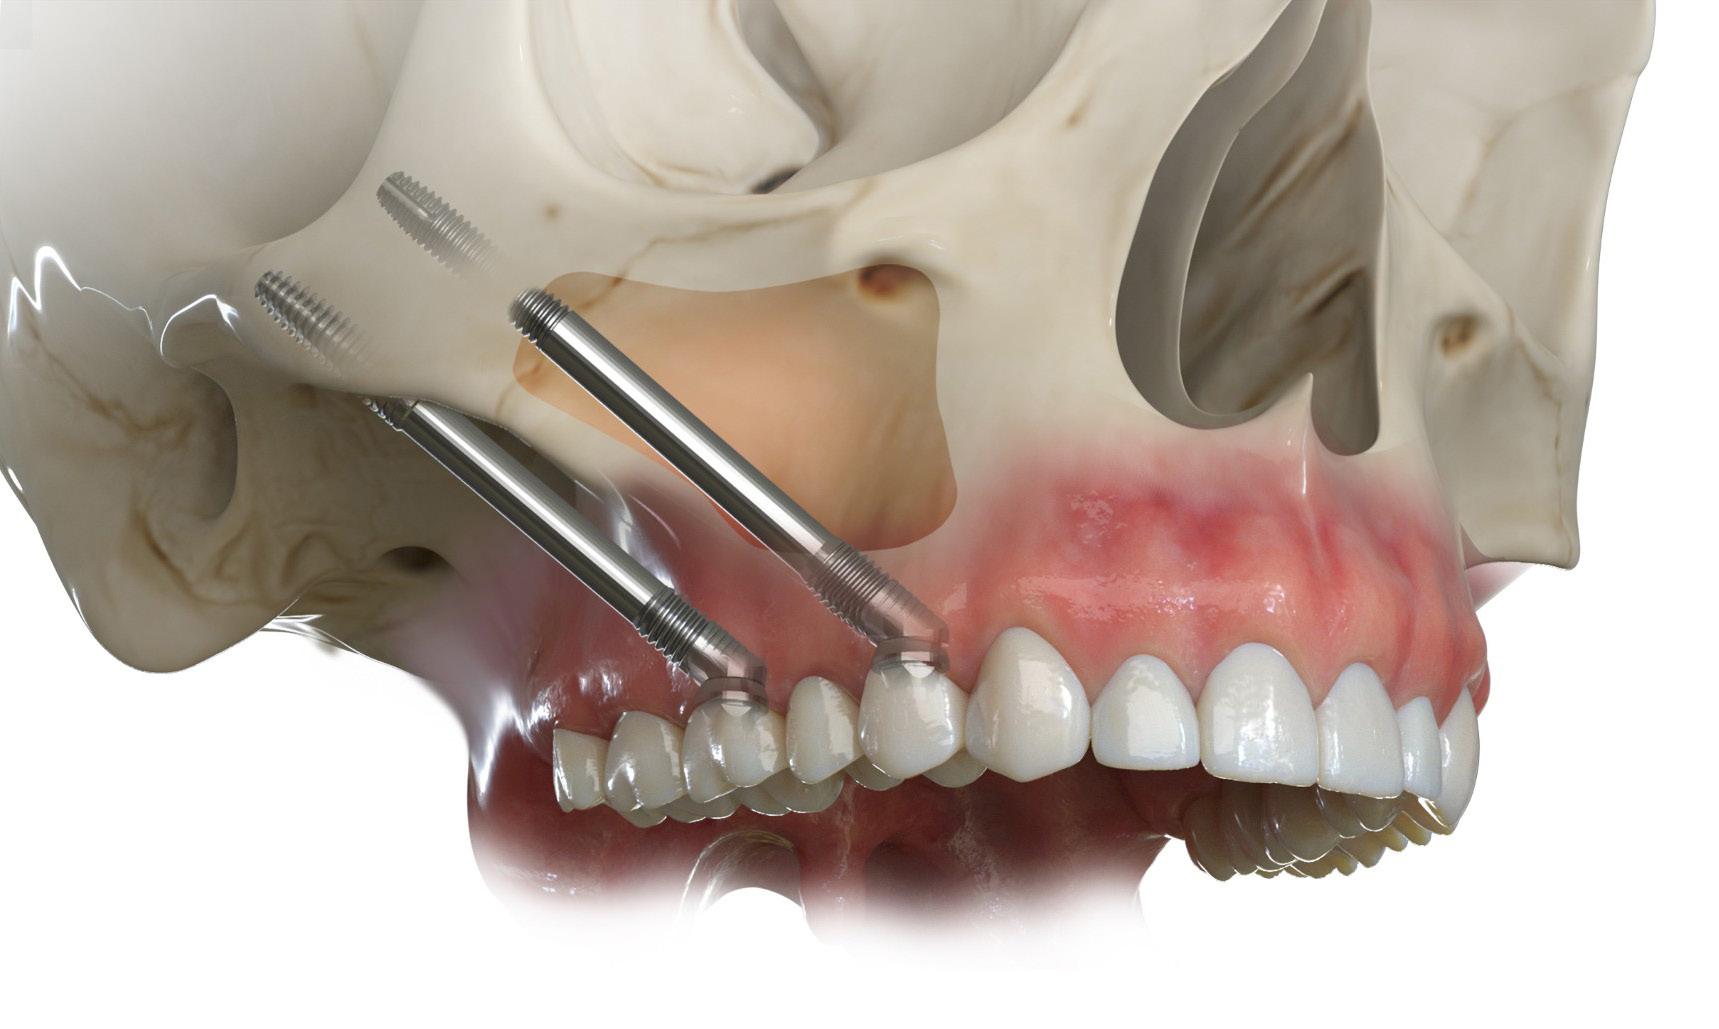

SOLUŢII PENTRU

CAZURI COMPLEXE ÎN IMPLANTOLOGIE

În implantologie, fiecare detaliu poate influența rezultatul final. GURSK a integrat în portofoliu sistemele Southern Implants, recunoscute internațional pentru abordarea inovatoare a cazurilor

complexe și pentru compatibilitatea cu principiile biologice moderne.

Implanturile zigomatice Southern Implants (fig. 1) oferă soluții sigure pentru reabilitarea maxilarelor cu atrofie severă, prin ancorare în osul zigomatic, putând elimina necesitatea grefelor osoase în multe cazuri selectate. Disponibile în lungimi de 30–60 mm, cu opțiuni Co-Axis® 55° pentru corecția angulației, asigură stabilitate și emergență protetică optimă. Suprafața SInergy™ sprijină osteointegrarea, iar zona MSC (Machined Surface Coronal) reduce riscul de periimplantită. Selectarea se realizează conform protocolului

ZAGA, pentru o adaptare precisă la anatomia pacientului.

Implanturile pterigoidiene

Southern Implants (fig. 2) sunt concepute pentru inserare la un unghi de 45–60°, oferind ancorare sigură în osul cortical pterigoidian și stabilitate ridicată chiar și în cazurile de atrofie severă. Designul conic, cu vârf îngust și filet auto-tăietor, permite inserție controlată în os cortical dens, iar încărcarea imediată este posibilă în funcție de stabilitatea primară obținută. Conexiunea Deep Conical asigură etanșeitate între implant și componenta protetică, iar suprafața tratată SInergy™

sprijină osteointegrarea rapidă și durabilă.